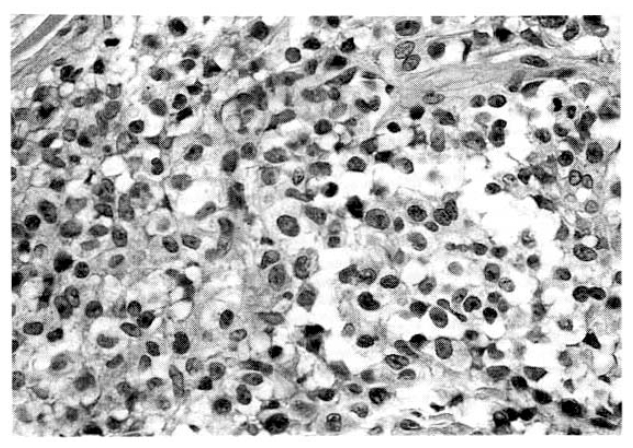

Fig. 3.

Skin biopsy shows the dermis diffusely infiltrated with large pleomorphic tumor cells seen in lymph node (H & E stain, ×200).

Fig. 4.

Tumor cells are strongly positive for Ki-1(immunohistochemical stain, ×200).

Laboratory evaluation revealed hemoglobin of 7.4g/dl, hematocrit of 22.4 percent, leukocyte of 14,600/mm3 with 66 percent neutrophils and 8 percent lymphocytes and platelet 300,000/mm3. The erythrocyte sedimentation rate was 71 mm/hour. Results of serum chemistry test were normal with exception of LDH 1003.3IU/I, BUN 29.9mg/dl, creatinine 1.9mg/dl. The electrocardiography was normal. Radiologic examination of chest revealed fibrostreaky densities in right upper lobe and CT scan of abdomen showed no intra-abdominal lymphadenopathy. Biopsy of cutaneous lesions on anterior chest wall and bone marrow aspiration and biopsy were performed. Light microscopic examination of skin specimen showed that the dermis was diffusely infiltrated with large pleomorphic tumor cells, which were strongly positive for Ki-1 immunohistochemical stain (Fig. 3, 4). Electromicroscopic examination revealed convoluted nuclei with prominent nuclei and sparse intracytoplasmic organelles (Fig. 5). Bone marrow aspiration and biopsy showed a focus of collection of atypical cells with complete necrosis, suspicious for involvement of malignant lymphoma. On diagnosis of relapsed Ki-1-positive anaplastic lymphoma stage IV, we performed salvage chemotherapy with cisplatin, dexamethasone, mitoxantrone and etoposide but, unfortunately, he died of persistent pancytopenia, followed by sepsis.